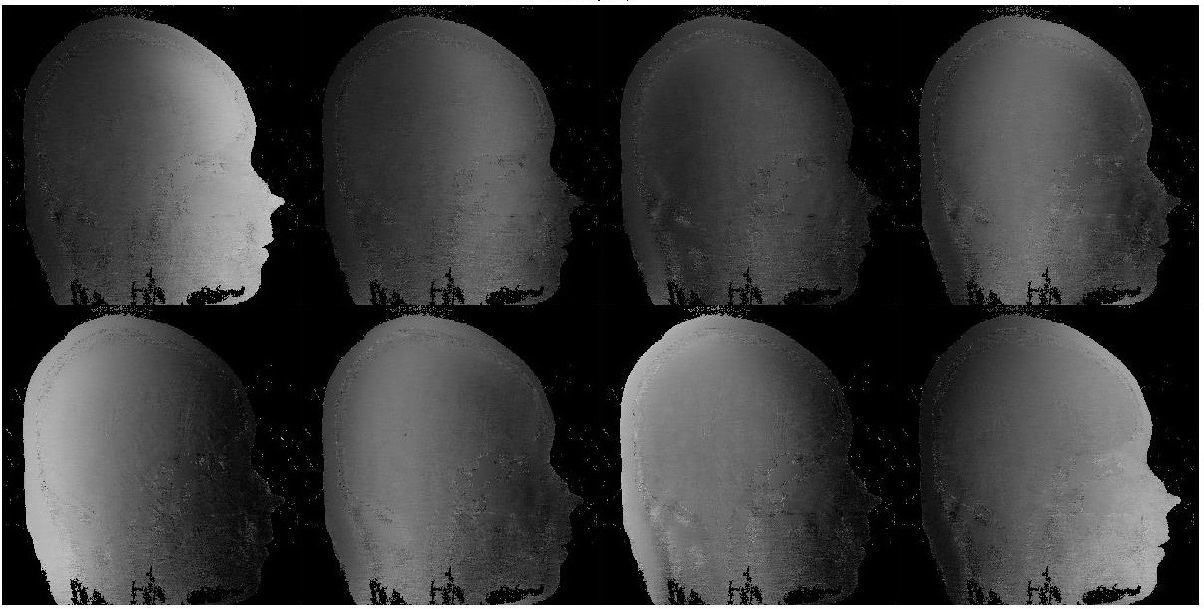

5.3 Partially parallel imaging

In this subsection, we compare the performance of the FUSL method with several related algorithms in reconstruction of magnetic resonance (MR) images from partial parallel imaging (PPI), to further confirm the observations on advantages of this method. The detailed background and description of PPI reconstruction can be found in [6]. This image reconstruction problem in two dimensional cases can be modeled as

where is the vector form of a two-dimensional image to be reconstructed, is the number of MR coils (consider them as sensors) in the parallel imaging system. is a 2D discrete Fourier transform matrix, is the sensitivity map of the -th sensor, and is a binary mask describes the scanning pattern. Note that the percentages of nonzero elements in describes the compression ration of PPI scan. In our experiments, the sensitivity map is shown in Figure 3, the image is of size shown in Figures 4 and 5, and the measurements are generated by

where are the noise with entries independently distributed according to . We conduct two experiments on this data set with different acquisition rates, and compare the FUSL method to NEST-S method, and the accelerated linearized alternating direction of multipliers (AL-ADMM) with line-search method [25].

For both experiments, set , and are generated by (5.6). In the first experiment, we use Cartesian mask with acquisition rate : acquire image in one row for every successive seven rows, while for the second one, we use Cartesian mask with acquisition rate : acquire image in one row for every successive ten rows. The two masks are shown in Figure 3. The results of the first and second experiment are shown in Figures 4 and 5 respectively. These experiments again demonstrate the advantages of the FUSL method over these state-of-the-art techniques for PPI image reconstruction,